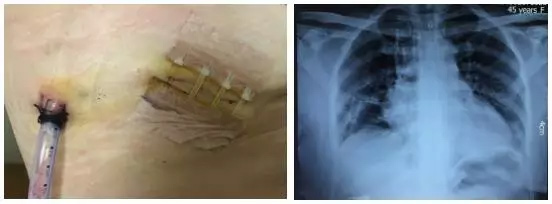

手术过程顺利,术中出血约30ml,手术切口小,创伤小,术后患者疼痛较轻,咳嗽有力,术后第二天复查胸片,显示右肺复张良好,遂拔除胸管,患者术后第4天出院。患者恢复顺利,住院时间短。手术切口及术后胸片如下图所示。